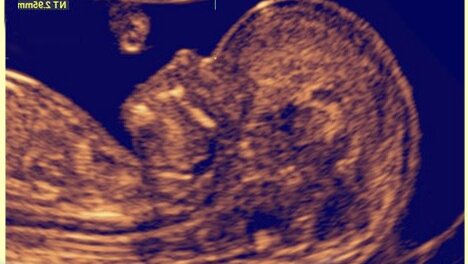

«Толщина воротникового пространства плода». Почему беременные боятся проходить это исследование